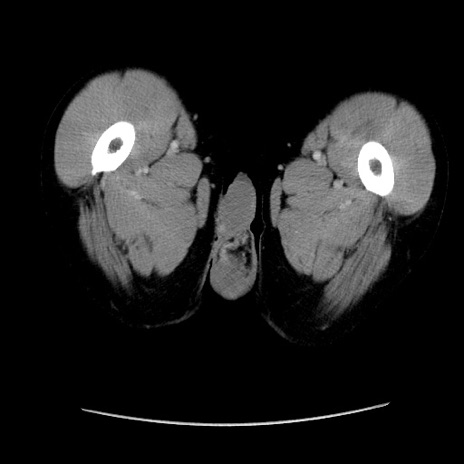

症例37(横断像)

【症例】40歳代 男性

【主訴】腹痛

【現病歴】4時間ほど前に電車に乗車中に臍部上より腹痛出現。徐々に増悪し起立困難となり、救急外来受診。生ものは数日食べていない。今朝お雑煮を食べた。

【身体所見】BT 36.8℃、BP 117/84mmHg、HR 91/min、SpO2 97%、苦悶様、腹部:臍上部広範囲圧痛あり、反跳痛±

【データ】WBC 8100、CRP 0.03